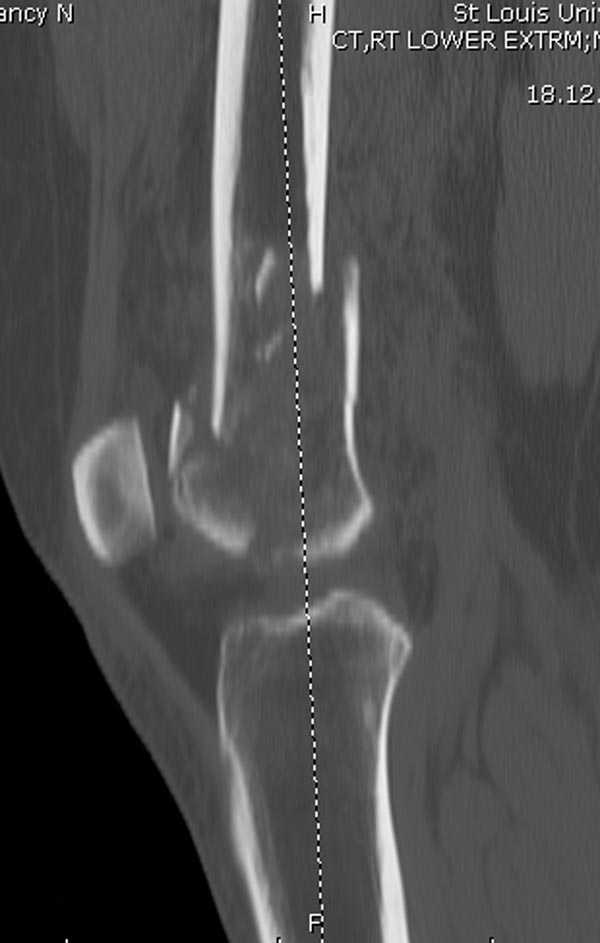

Бесспорно, предлагаемый ретроградный метод имеет свои преимущества, но имеется опасность при манипуляции интрамедуллярным гвоздем расколоть мыщелки.

Раскол можно предупредить шурупами, но короткий дистальный фрагмент навряд ли позволит добиться адекватной стабильности конструкции. Стандартные гвозди не рассчитаны для таких переломов, и если все таки желаете провести фиксацию гвоздем, тогда надо заказывать специальный custom made nail т.е. с расширенной возможностью дистальной блокировки.

Поэтому такие меж и над- мыщелковые переломы более предпочтительным считается фиксировать мыщелковыми пластинами

Устанавливается из малого разреза "не вскрывая сустав" со стороны латерального мыщелка, и Insertion Jig позволяет установить пластину "мостовидно" перкутанно в проксимальном отделе, "не вскрывая и не трогая" место перелома.